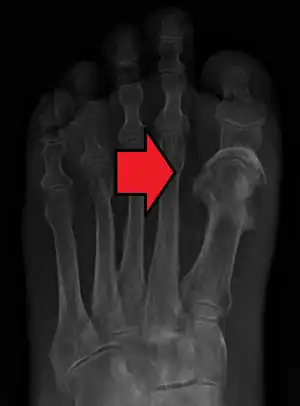

Osteomyelitis of the 1st toe

Extensive osteomyelitis of the forefoot